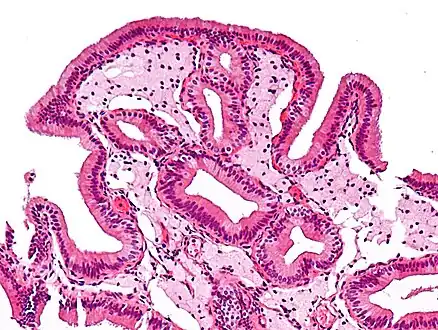

Micrograph of cholesterolosis of the gallbladder